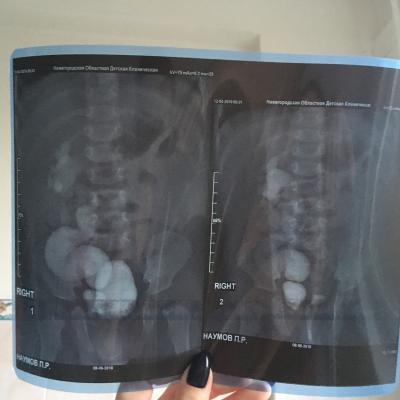

Здравствуйте , с Рождения поставлен диагноз уретерогидронефроз , пмр4 ст. Пол года назад сделали операцию по Коэну, но улучшений нет , рефлюкс стал 3 ст, а функция почки снижена . Лечащий хирург сказал, что ничего предпринимать не нужно, только наблюдение и высокая вероятность сморщивание почки и в последствии ее удаление. Скажите пожалуйста действительно ли уже не спасти почку ?!

Прилагаю снимки до операции и после операции.